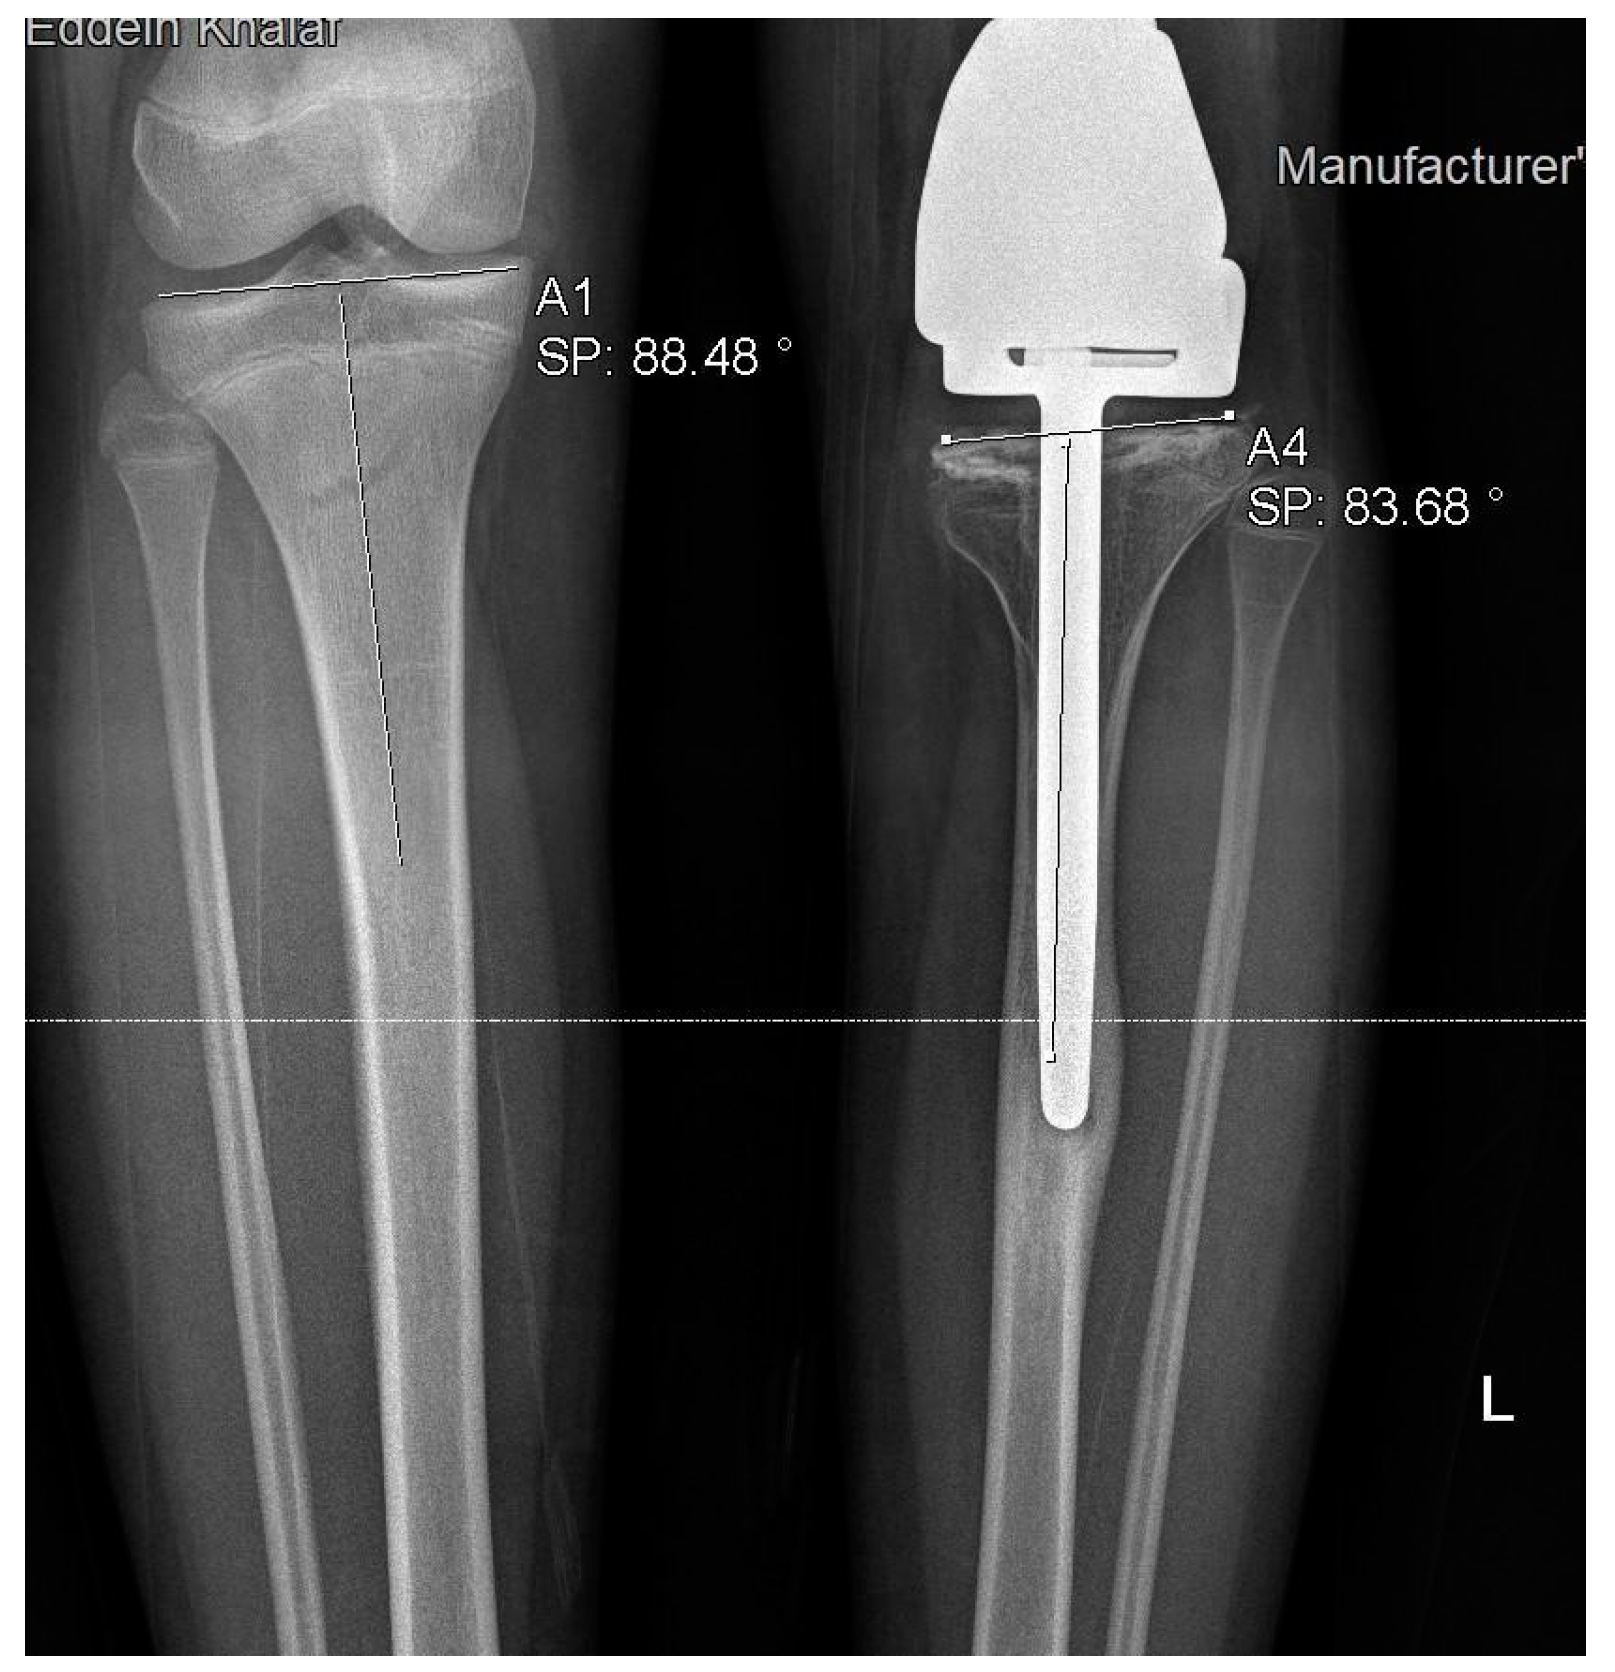

3.5. Rotational and Angular Deformities

Eleven patients had tibia rotational deformities with a mean difference of 13.4 degrees (632 degrees) between the operative and contralateral sides (Figure 5). Coronal deformities were detected in three patients, with a mean MPTA of 80.3 degrees (77–83 degrees) (Figure 6). One patient had a sagittal deformity of PTSA six degrees.

Figure 5.

Rotational deformity of 26 degrees in one of our patients.

Figure 6.

Coronal varus deformity in one of our patients.